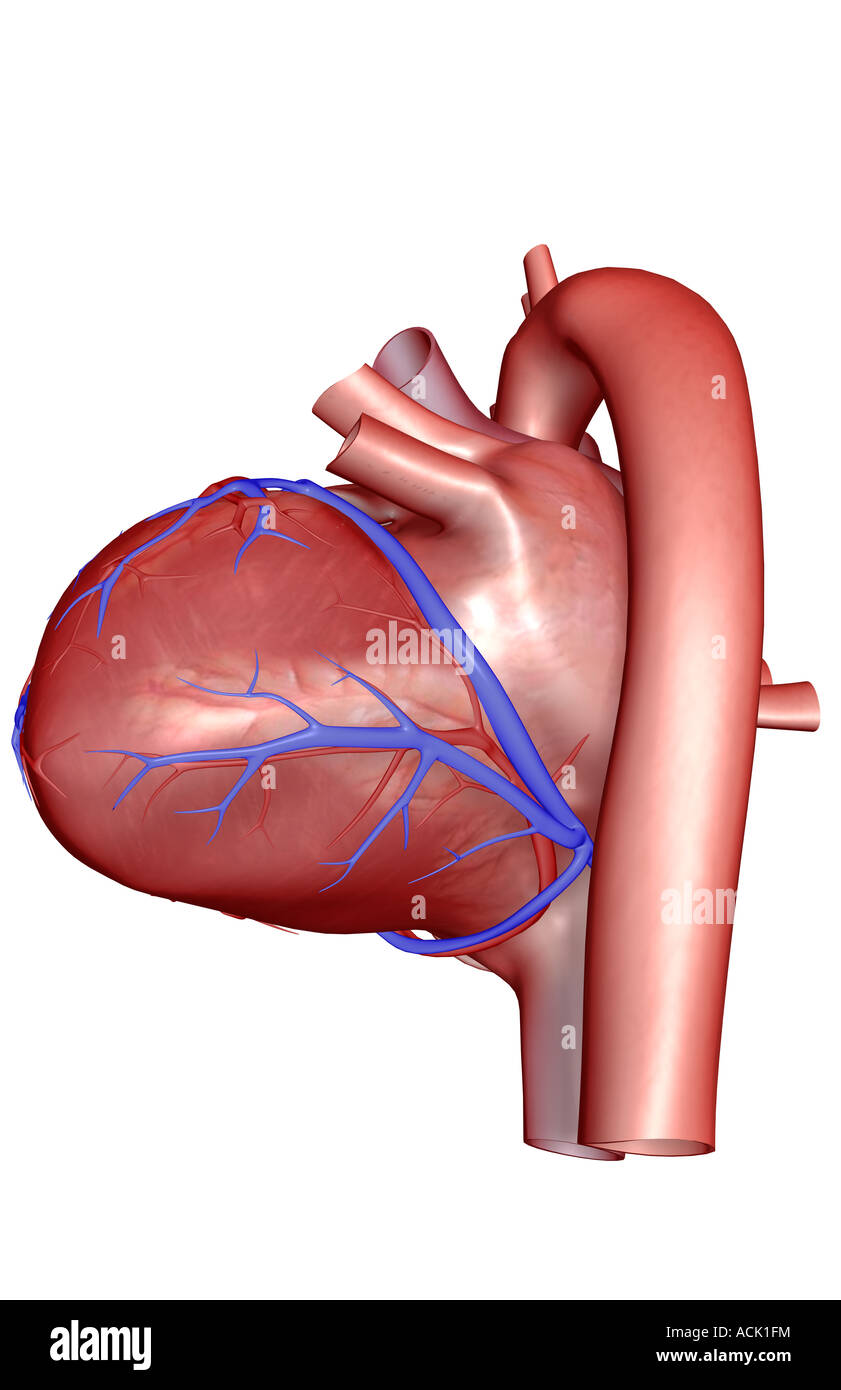

The coronary vessels of the heart Stock Photohttps://www.alamy.com/image-license-details/?v=1https://www.alamy.com/stock-photo-the-coronary-vessels-of-the-heart-13174855.html

The coronary vessels of the heart Stock Photohttps://www.alamy.com/image-license-details/?v=1https://www.alamy.com/stock-photo-the-coronary-vessels-of-the-heart-13174855.htmlRFACK1FM–The coronary vessels of the heart